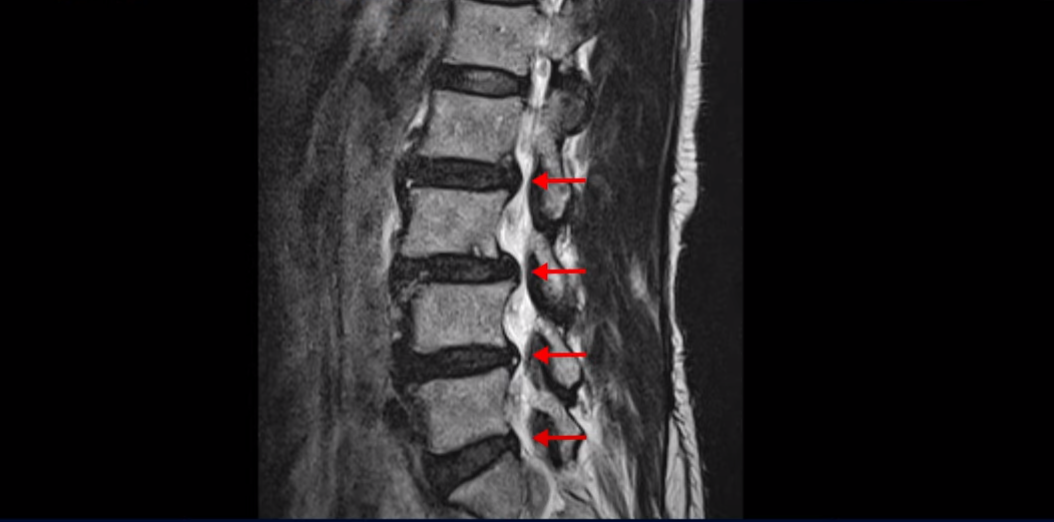

이분 허리를 보면 여러 마디의 퇴행성 디스크와 협착이 있습니다.

2번 3번과 3번 4번은 신경다발이 지나가는 척추관도 좁아져 있습니다.

또 3번 4번에는 척추뼈가 밀려나간 전방전위증도 있습니다.

이분은 정형외과 병원에서 3마디 디스크 파열이라고 수술 권유를 받았는데 저희는 디스크 파열은 잘못된 진단이라고 봅니다. 여러 마디 보이는 디스크 문제는 파열이 아닌 퇴행성디스크들이고 아픈 원인은 전방전위와 협착증 증상입니다. 전방전위와 협착증이긴 하지만 아주 심한 게 아니고 발병한지도 얼마 되지 않아서 근육재활치료를 하면 2주 정도면 빨리 호전될 수 있는 상태였습니다. 왜 이런 환자가 치료하기 훨씬 쉬운 건지, 치료는 어떻게 하는 건지 지금부터 설명 드립니다.

이분이 처음 발병한 건 저희 치료를 시작하기 불과 2주 전입니다. 만일 이분이 아프기 전인 몇 달 전에 MRI를 찍었다면 지금 보시는 MRI와 많이 다를까요? 정답은 전혀 차이가 없다입니다. 뼈가 밀려나가고 신경 구멍이 좁아진 건 이미 오래 전에 벌어진 일입니다. 뼈가 밀려나가고 신경 구멍이 좁아져 있는 채로 아무런 증상을 느끼지 않고 66세까지 잘 산 것입니다. 이런 걸 잠복 협착이라고 합니다. MRI로 협착이 보이지만 아무런 증상이 없다는 뜻입니다.